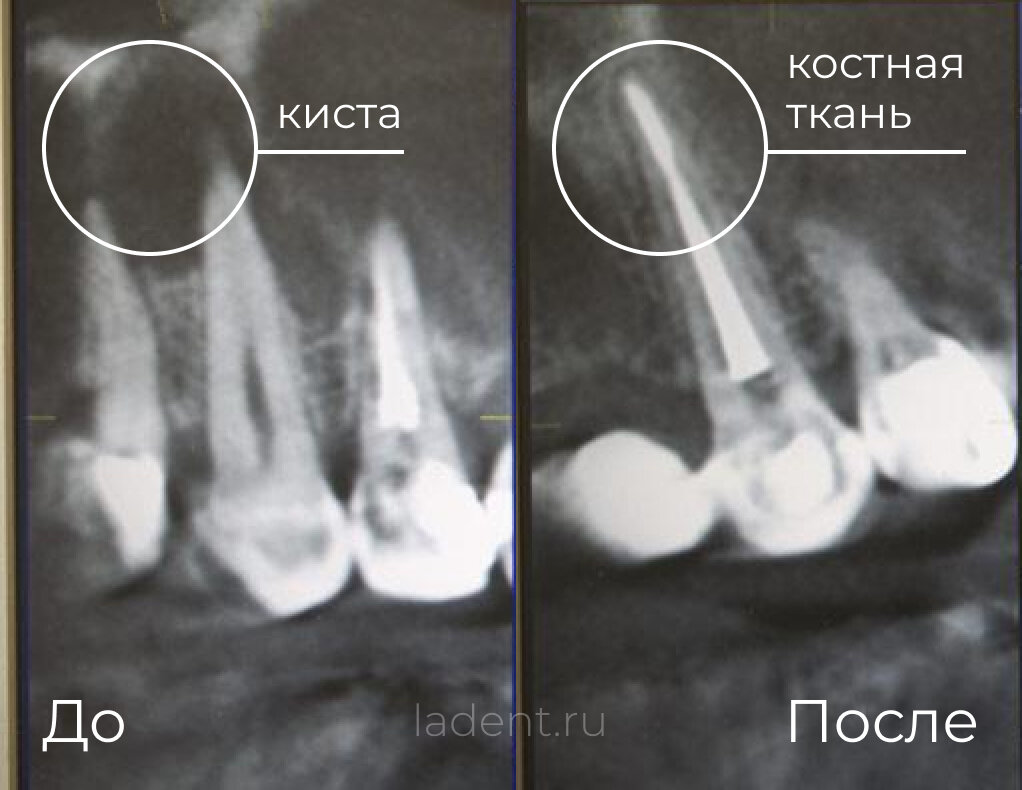

"Нужно удалять зуб" — такой вердикт еще недавно был почти неизбежен при обнаружении кисты. Однако стоматология не стоит на месте. Появление новых технологий и методик позволяет сохранить зуб даже в сложных случаях. Рассмотрим, какие современные решения существуют сегодня и почему диагноз "киста" больше не означает потерю зуба.

Стоматология прошла большой путь в лечении зубов с кистой. Если раньше врачи часто выбирали удаление как наиболее предсказуемый метод, то сегодня у специалистов есть инструменты, позволяющие работать с исключительной точностью и сохранять зубы, которые еще недавно считались безнадежными.